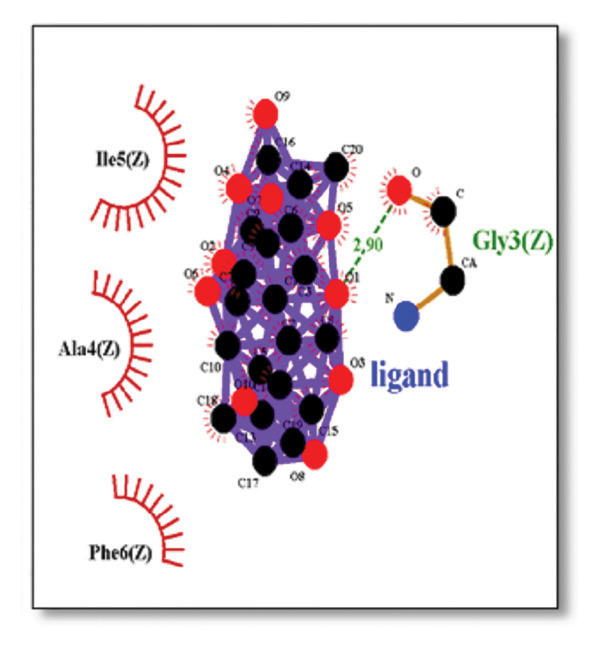

Against the core Aβ peptide, ginkgolide again showed the lowest binding energy (−8.40 kcal/mol), though no direct hydrogen bond interactions were detected in the lowest‐energy pose. Ginsenosides (−4.36 kcal/mol) demonstrated stable interactions, notably forming H‐bonds with ALA4 and LYS2.

Ginsenosides (−4.36 kcal/mol) formed a highly optimal bond with ALA4 (carbonyl oxygen [O] donor) with a short distance (2.56 Ǻ) and a near line angle (160.82°). Cyanidin (−3.94 kcal/mol) also formed H‐bonds with ILE5 and ASN1. The reference drug memantine exhibited significant binding at −3.56 kcal/mol, forming an H‐bond with the critical amyloidogenic residue ILE5 D‐A 2.80 Ǻ, angle: 159.52°. Figure 4 summarizes the binding characteristics for Aβ peptide.

Beyond ginkgolide, several other natural product‐derived ligands demonstrated significant multitarget potential, reinforcing the growing recognition of phytocompounds as rich sources for complex disease therapeutics. Ginsenosides, core triterpenoid saponins from ginseng, showed strong binding to sortilin, clusterin, and Aβ peptide. The computational modeling and molecular docking simulations performed in this study identified ginsenosides that exhibit a strong binding affinity for several key AD receptors. This novel finding is well‐supported by prior in vivo literature, which demonstrates the neuroprotective efficacy of these compounds. The docking analysis revealed specific molecular‐level interactions that underpin this strong binding. For instance, ginsenosides were found to interact with the sortilin receptor, forming key contacts with amino acid residues ILE141 and MET139. The functional significance of this interaction is that these hydrophobic residues are positioned at the entrance or periphery of the main ligand cavity. Binding here suggests an allosteric modulatory mechanism, where the ginsenosides could induce a conformational shift that impacts sortilin’s crucial role in the trafficking and endocytosis of the amyloid precursor protein (APP), potentially leading to reduced Aβ production and clearance [ref. 45]. The binding of ginsenosides at these specific residues could therefore modulate sortilin’s function, leading to reduced Aβ pathology.

Similarly, interactions with the clusterin receptor (also known as ApoJ) were mediated through a crucial binding site involving PHE240. PHE240 is a key hydrophobic residue within clusterin’s large chaperone domain. Our findings suggest that ginsenosides use a hydrophobic interaction at this specific residue to modulate the chaperone activity, thereby potentially stabilizing clusterin in a conformation that effectively prevents $\text{A}\beta$ from forming toxic oligomers [ref. 46]. Aβ peptide ginsenosides were shown to interact directly with ALA4 and LYS2. These particular residues are located in a critical hydrophobic region of the Aβ peptide, which is essential for its initial self‐association and subsequent aggregation into neurotoxic oligomers and fibrils. The ginsenoside interaction at these sites provides a compelling direct mechanism for how these compounds could inhibit Aβ aggregation, a central pathological event in AD [ref. 47].